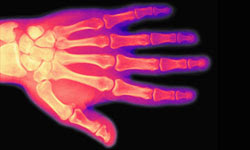

Wacky Facts Wednesday - Bone Count

An adult has fewerbonesthan a baby. We start off life with 350 bones, but because bones fuse together during growth, we end up with only 206 as adults.